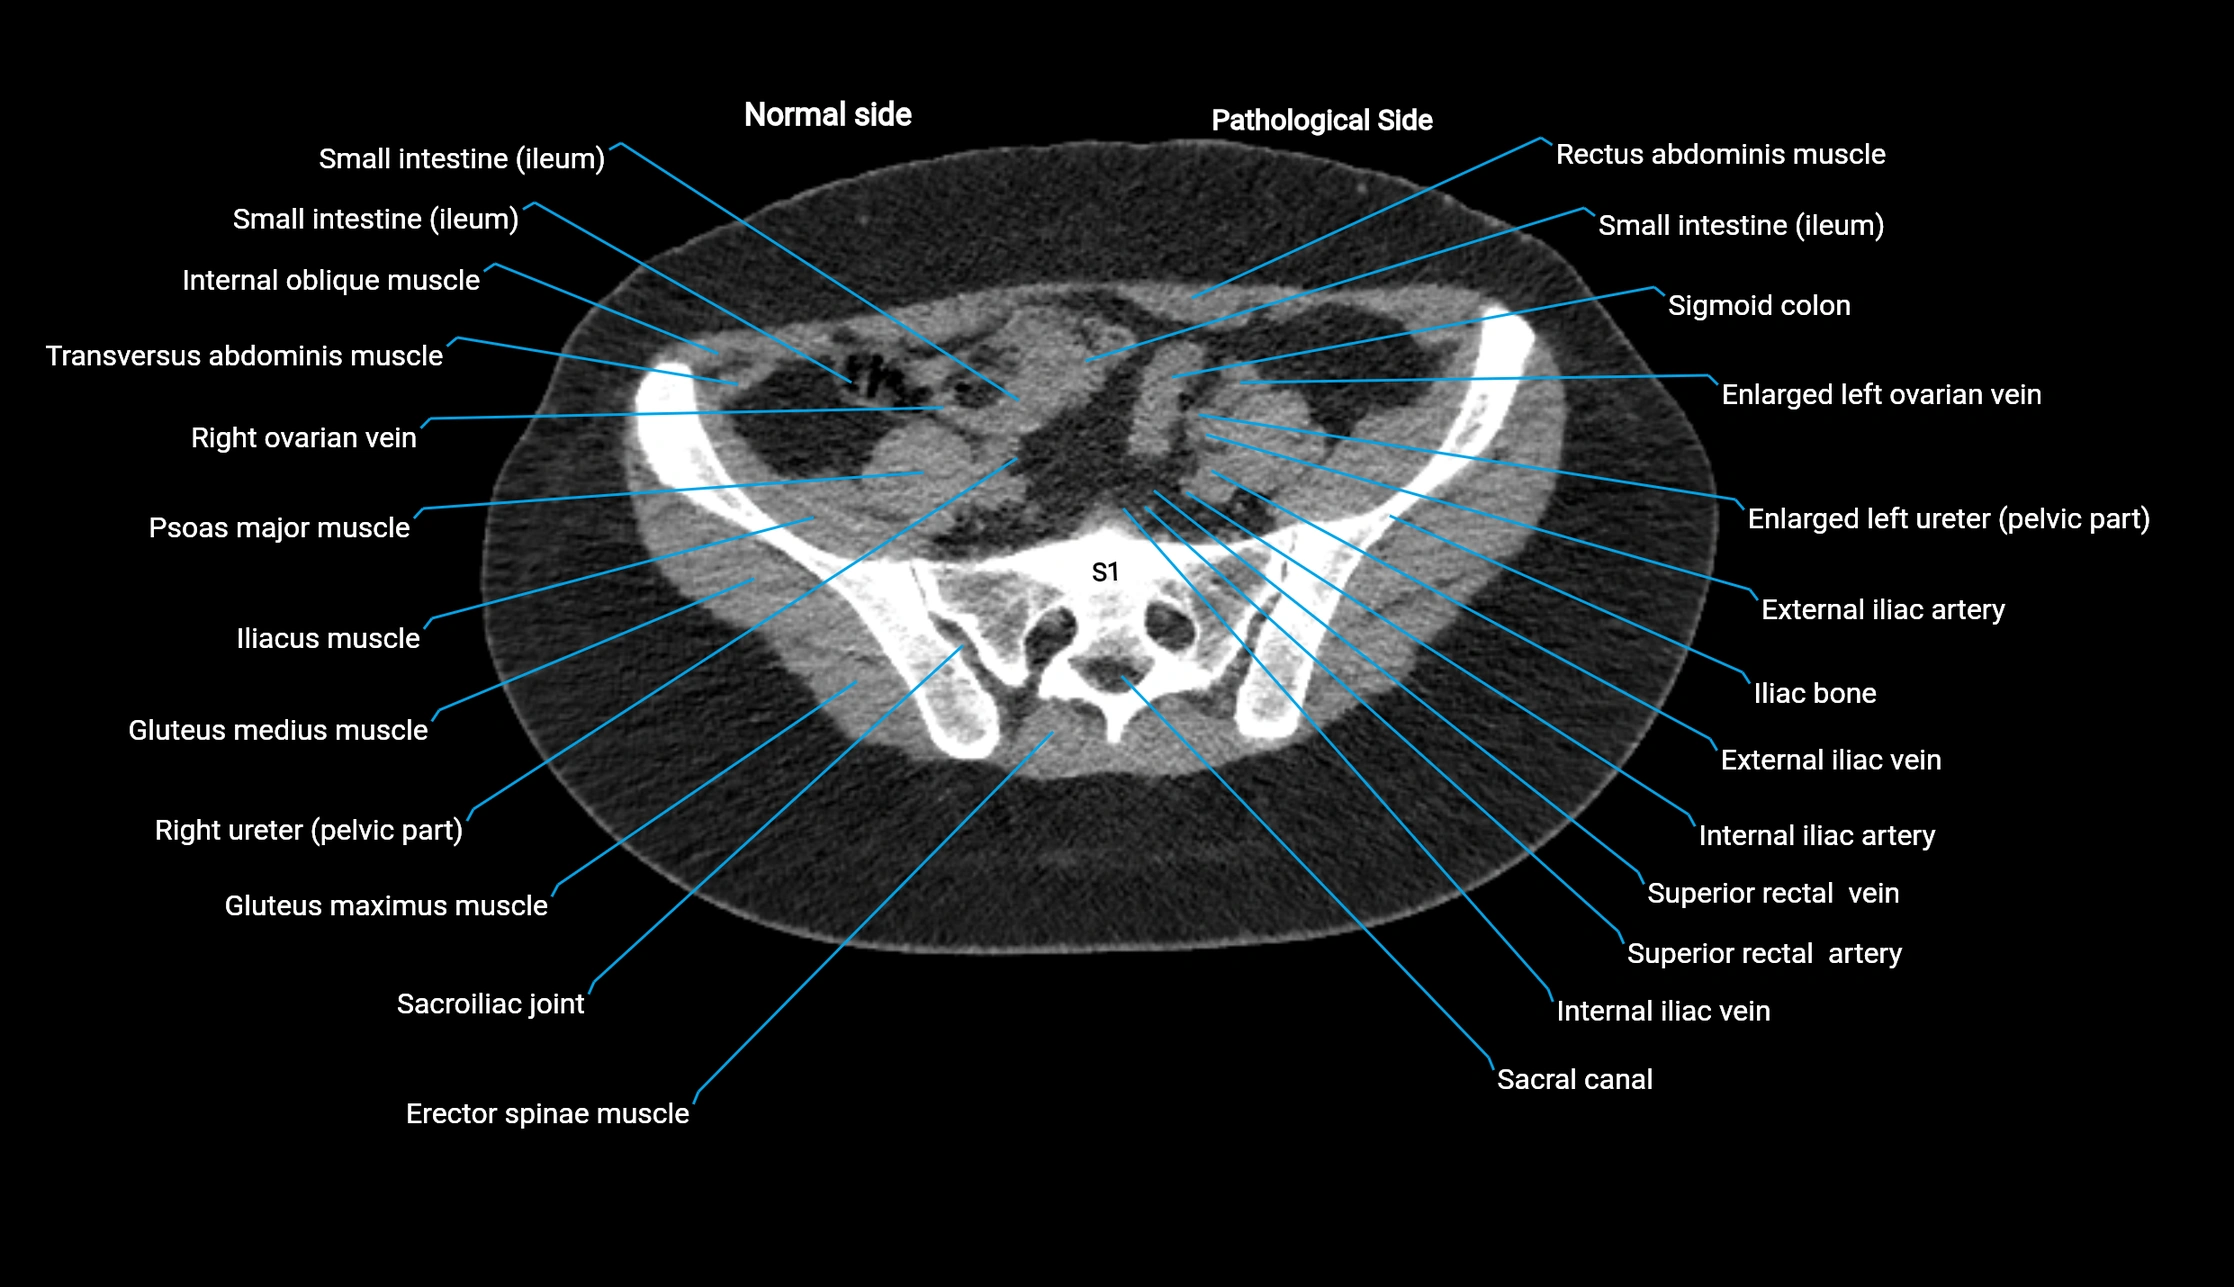

CT image

image